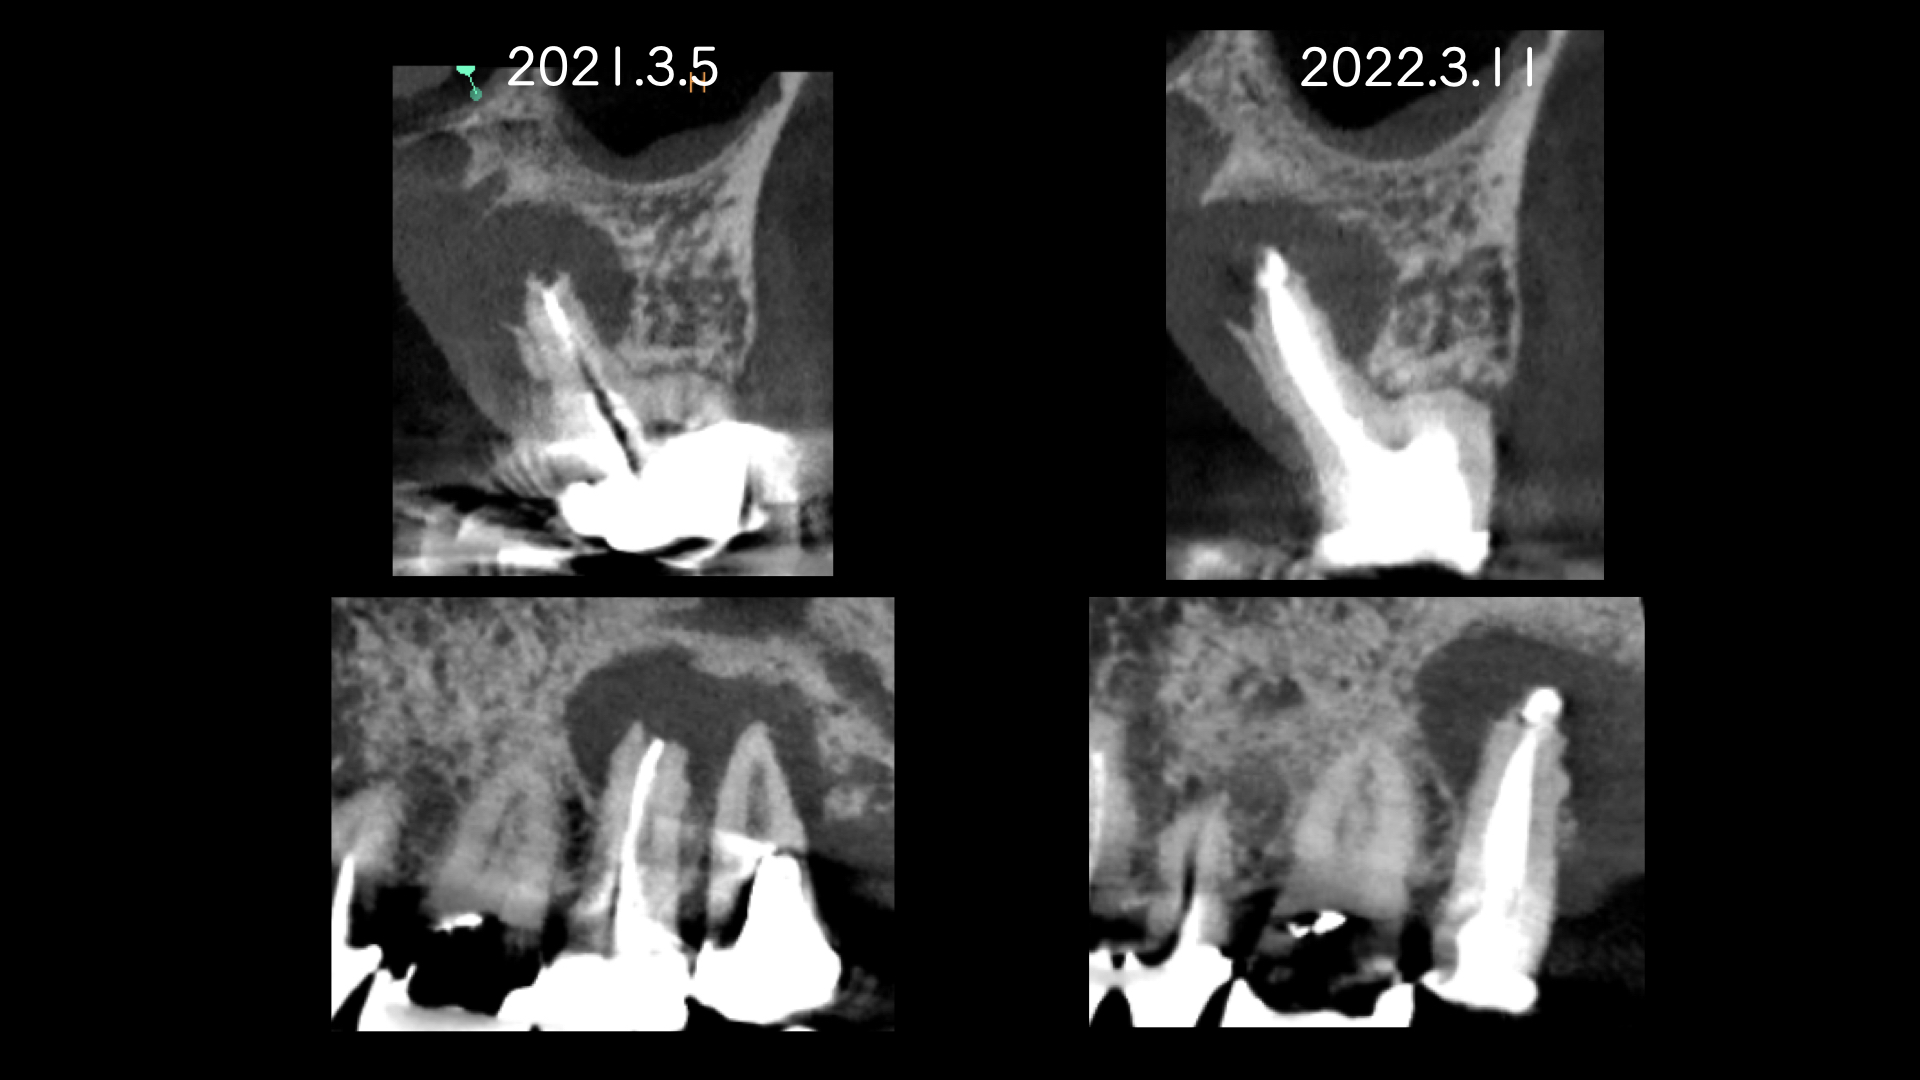

右の画像のCT上で根尖部にかなり大きな透過像があります。

根管治療はマイクロスコープを使用し、根管内は綺麗になった。と判断したので2回でMTAセメントにより根管充填をおこないました。

噛み合わせの反対側(下顎)はインプラント治療をおこなっており、経過をみていましたが全く変化がありませんでした。

患者さんの都合もあり1年後に歯根端切除(外科的歯内療法)をおこなうことになりました。

術後、歯根は骨に囲まれるように治癒にしました。